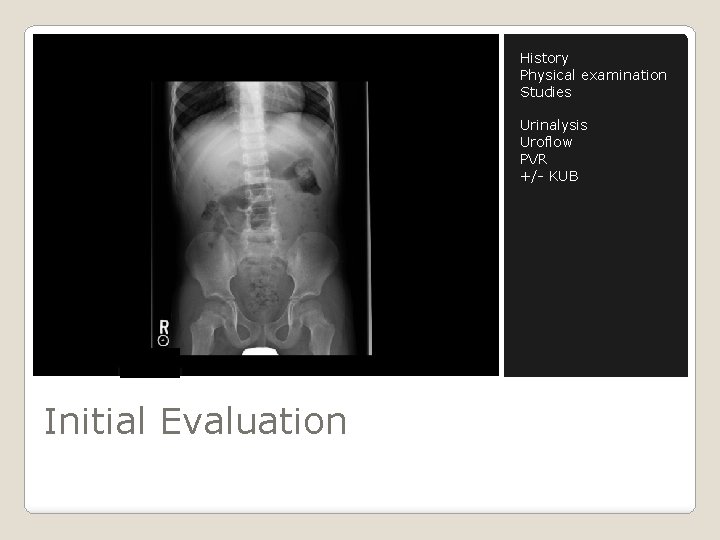

History Physical examination Studies Urinalysis Uroflow PVR +/- KUB Initial Evaluation

� � Urinalysis Uroflow Post-void bladder ultrasound +/- KUB � Renal ultrasound ◦ ◦ � Voiding cystourethrogram (VCUG) ◦ � never achieved a dry day after complying with program Cystoscopy ◦ � order if urodynamics abnormal Video urodynamics ◦ � Febrile UTIs MRI of the spine ◦ � hematuria Recurrent UTIs greater than 15 years of age with hematuria Urethral dilation is not recommended Medical Tests Available